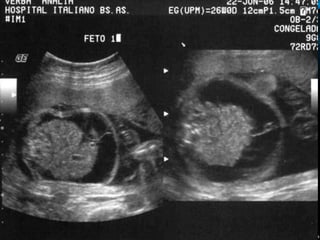

IDIOPÁTICO.

PACIENTE DE 19 AÑOS DE EDAD, III GESTA, II PARA,

FUM: INCIERTA, EMBARAZO ECOGRÁFICO DE 20

SEMANAS + HF.

ESTUDIO CITOGENÉTICO MEDIANTE AMNIOCENTESIS:

CARIOTIPO NORMAL 46 XY.

ECOCARDIOGRAFÍA FETAL NORMAL, VDRL (-), HIV (-).

SE DECIDE CONDUCTA EXPECTANTE, LAS EVALUACIONES

SUCESIVAS NO TUVIERON CAMBIOS.

A LAS 29,3 SEMANAS DESAPARICIÓN DEL HF Y CRECIMIENTO

FETAL EN P50.

A LAS 37 SEMANAS INICIA TRABAJO DE PARTO Y SE OBTIENE

RN NORMAL MASCULINO, PRODUCTO DE PARTO

EUTÓCICO, QUE PESA 2650 G., APGAR 9 PUNTOS.